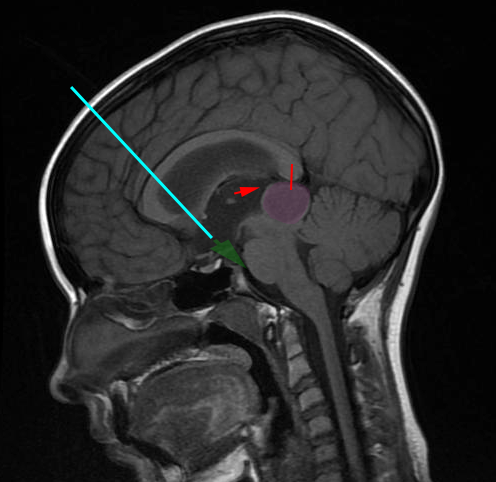

Η ενδοσκοπική τρίτη κοιλιοστομία είναι η διάνοιξη μιας μικρής οπής στο έδαφος την 3ης κοιλίας του εγκεφάλου προκειμένου να παροχετευθεί εγκεφαλονωτιαίο υγρό (Ε.Ν.Υ) από το κοιλιακό σύστημα στις βασικές δεξαμενές του εγκεφάλου . Είναι μια επέμβαση που πραγματοποιείται σε ασθενείς με αποφρακτικό υδροκέφαλο ως εναλλακτική λύση, σε ορισμένες περιπτώσεις, στην τοποθέτηση κοιλιοπεριτοναϊκής βαλβίδας εγκεφάλου. Το κύριο πλεονέκτημα της είναι η απουσία εξάρτησης από το κοιλιοπεριτοναϊκό σύστημα παροχέτευσης του Ε.Ν.Υ.

Η επέμβαση γίνεται με τον ασθενή υπό γενική αναισθησία. Η προσπέλαση στο κοιλιακό σύστημα του εγκεφάλου γίνεται μέσω μικρής κρανιοτομίας, συνήθως δεξιά μετωπιαία, και με την βοήθεια ενδοσκοπίου. Η οπή από την οποία παροχετεύεται το Ε.Ν.Υ. γίνεται στο έδαφος της τρίτης κοιλίας του εγκεφάλου με την βοήθεια ειδικού καθετήρα.